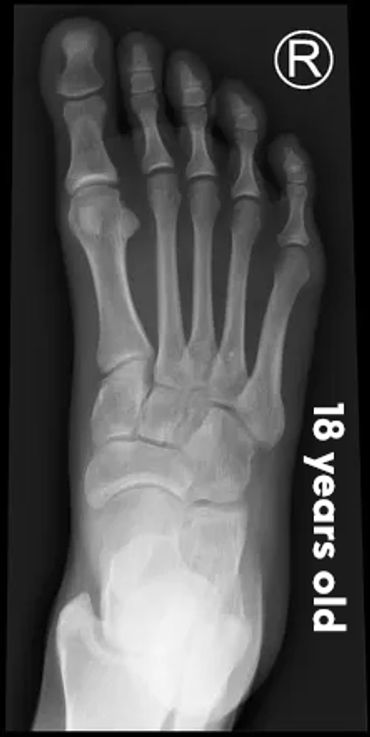

Let's check what their foot bones look like.

Pictures below will let you understand how babies' feet are developed.

Dear parents, children’s feet are developing structures, and the absence of an arch is a typical stage of development. The developing foot is not structurally ‘flat’; it is a highly compliant and plastic, that can respond to multiple factors, many of which we do not understand. Detailed X-RAY pictures above, let us understand that babies' foot bones are not connected till the teen years. Only at the age of 14, we may consider that the bones in the feet are developed and have reached their connections.

At the age of 18, we have fully completed foot structure, where muscles and bones create the whole support system.